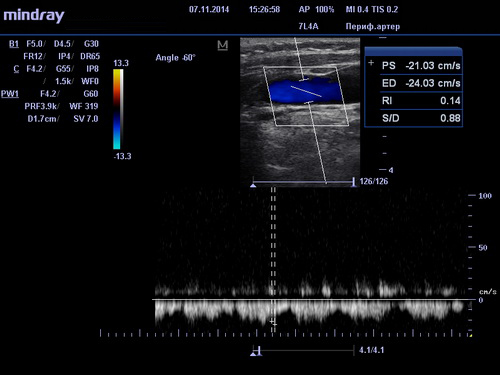

УЗИ сосудов в клиниках DoktorRU проводится по технологии, за основу которой взят эффект Допплера. Его суть заключается в том, что о состоянии и положении объекта можно судить по ширине волны, исходящей от него при движении. Это открытие дало возможность исследовать такие мельчайшие объекты как кровяные тельца в движении. УЗИ сосудов при использовании допплерометрии (или как ее еще называют, Допплерографии) позволяет получать очень точную информацию о состоянии кровеносных сосудов и на ее основе выявлять заболевания даже на ранних, досимптомных стадиях. Поэтому УЗИ сосудов объективно можно считать важнейшим инструментом диагностики и профилактики сердечно-сосудистых заболеваний.